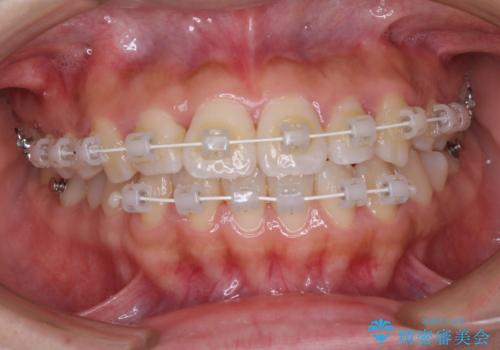

- 矯正装置

- 審美装置

- 上顎歯列と下顎前歯の叢生を気にして来院された患者様です。

上顎からワイヤー矯正を開始し、終了間際から下顎前歯の叢生解消するよう計画しました。

部分矯正でしたが、咬み合わせに違和感が出ることなく気になる部分を改善させることができました。